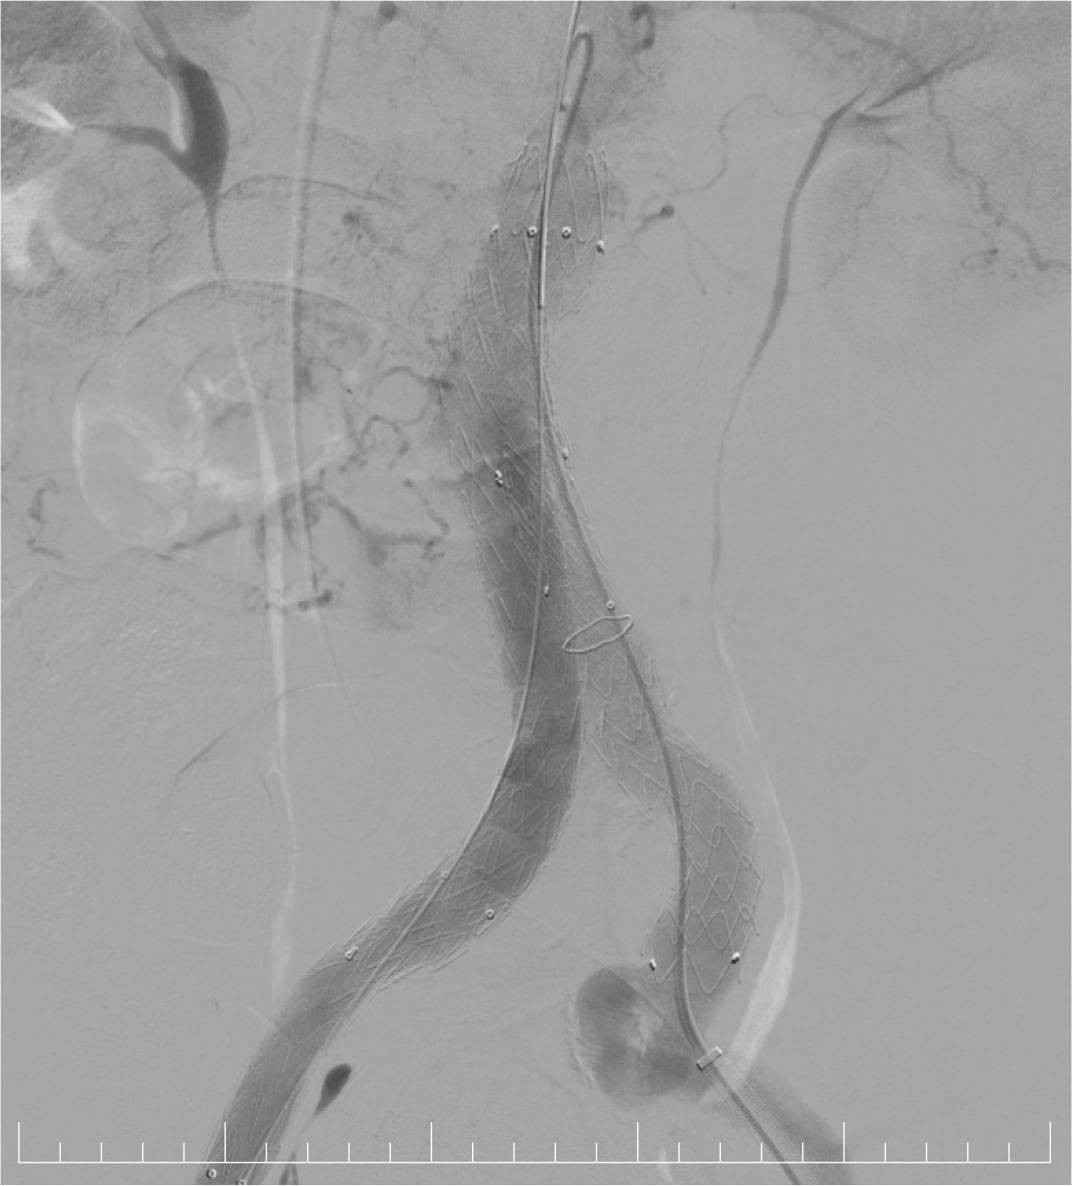

Afterwards, the procedure continued with the percutaneous implantation of an Endurant II 32-16-166 mm endograft from the origin of the right renal artery to the terminal abdominal aorta using a 18F Sentrant sheath. Completion with a left iliac extension was performed using an Endurant II 16-13-124 mm endograft from the terminal aorta to the proximal left ex-ternal iliac artery (EIA) – Figure 8.

Fluoroscopic image: EVAR successfully performed.

The graft was properly positioned and expanded with complete aneurysm exclusion and no visible leak. The right distal radial artery (5F sheath) was left in place for invasive blood pressure monitoring. Because the proper hemostasis was impossible to achieve at the femoral vascular access site, surgical hemostasis was necessary.